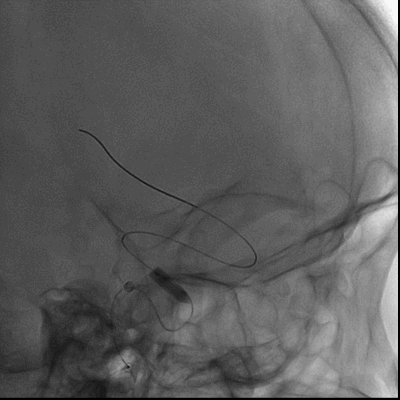

6F 115cm SKATHI远端通路导管与6F NeuronMax长鞘同轴,在泥鳅导丝引导下将SKATHI远端通路导管送至左侧颈内动脉海绵窦段。

山高路远,道路迂曲

SKATHI轻松通过